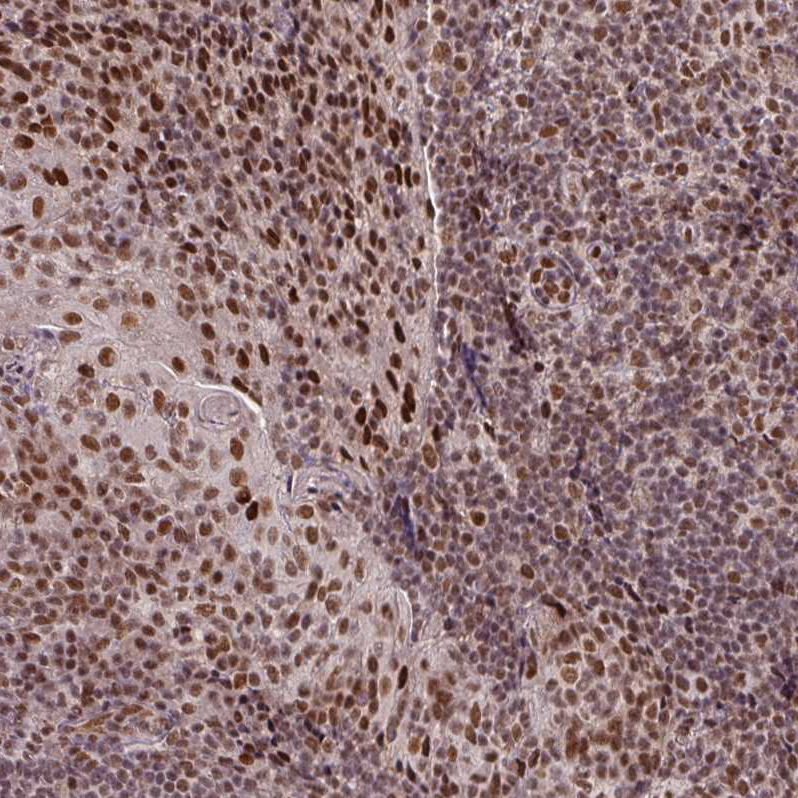

Immunohistochemical staining of human tonsil shows moderate to strong nuclear positivity in germinal center cells.